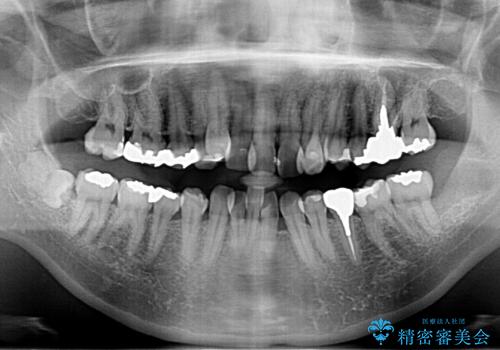

- 30代女性

- 治療期間

- 6ヶ月

- 治療回数

- 10-30回

- 当院で矯正治療後、虫歯治療を一通り行いました。

矯正治療後はリテーナーを使用する必要がありますが、両方同じ病院で行うことにより、リテーナーの再作成や修理もしっかり対応できます。